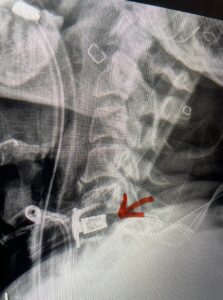

Another patient, a 77 year-old female, presents with pain, numbness, and weakness of her arms and difficulty with balance over a 6-month period. MRI revealed severe osteophytic disease at C5-C7 with cord compression (Fig. 4). Further work-up by fine-cut cervical CT to evaluate the nature of compression revealed a completely calcified osteophyte (Fig. 5). Although the patient had a good lordosis and a posterior cervical approach would accomplish an adequate decompression, we elected to perform a two-level anterior cervical discectomy and fusion. This particular osteophyte is formidable because of its size but the compression was all anterior and would be a less invasive approach. Fortunately, during the procedure, the patient had a fair amount of osteoporosis which allowed the osteophyte to be drilled and bit away with considerable ease. Interestingly, the C6 7 osteophyte which was more a sheet of osteophyte was more challenging to remove. In the end the decompression went well, and we placed two interbody devices filled with bone graft with plates at each level (Fig. 6). The patient had a nice recovery with immediate reduction of pain and numbness. This case demonstrates the importance of recognition of cervical myelopathy in its early stages. A significant reversal of function is generally the rule if the patient has appropriate correlative findings on exam and MRI, particularly with long tract distribution weakness development within a year time period.

Fig 6: Intraoperative lateral cervical x-ray demonstrating placement of interbody cages and plates